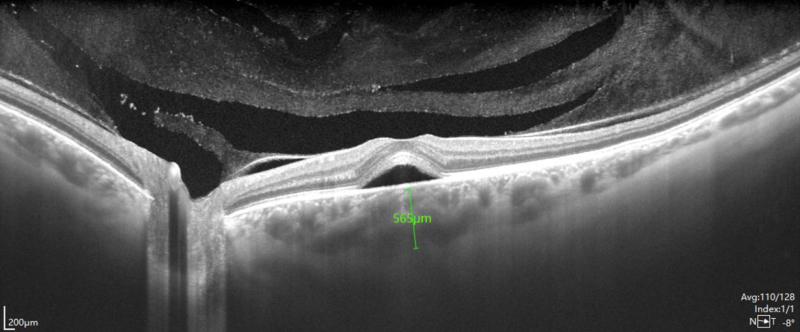

L’exploration de la rétine par OCT (Optical Coherence Tomography : Tomographie à cohérence optique) est un examen obtenu par un balayage par faisceau laser de faible énergie dont l’appareil analyse la réflexion à travers les différents tissus traversés : un équivalent d’échographie mais par principe optique. Les appareils modernes d’OCT se caractérisent par une très haute résolution des images (3 à 7 microns), ce qui permet de générer des images en coupes des différentes couches de la rétine au niveau de la région maculaire (partie de la rétine la plus fonctionnelle située directement sur l’axe visuel).

L’imagerie par OCT permet de détecter soit un épaississement de la rétine, soit la présence d’anomalie dans ou sous la rétine (œdème, néovaisseaux, atrophie, membrane…)

Les résultats sont exprimés en images en coupe de la rétine et en cartographies de la région maculaire.